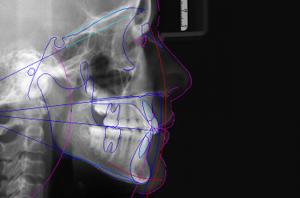

• Des radiographies : Panoramique (pour une vision d’ensemble de la denture et de l’évolution dentaire), de profil (pour voir les relations et décalages entre les mâchoires) et si nécessaire du poignet (pour estimer le stade de croissance du patient et la croissance résiduelle disponible) et de face (pour mettre en évidence des asymétries)

À partir des éléments de ce bilan orthodontique, le praticien va pouvoir analyser les données cliniques, les photos, les radiographies pour une analyse céphalométrique et les moulages pour établir un diagnostic précis et proposer un traitement adapté.